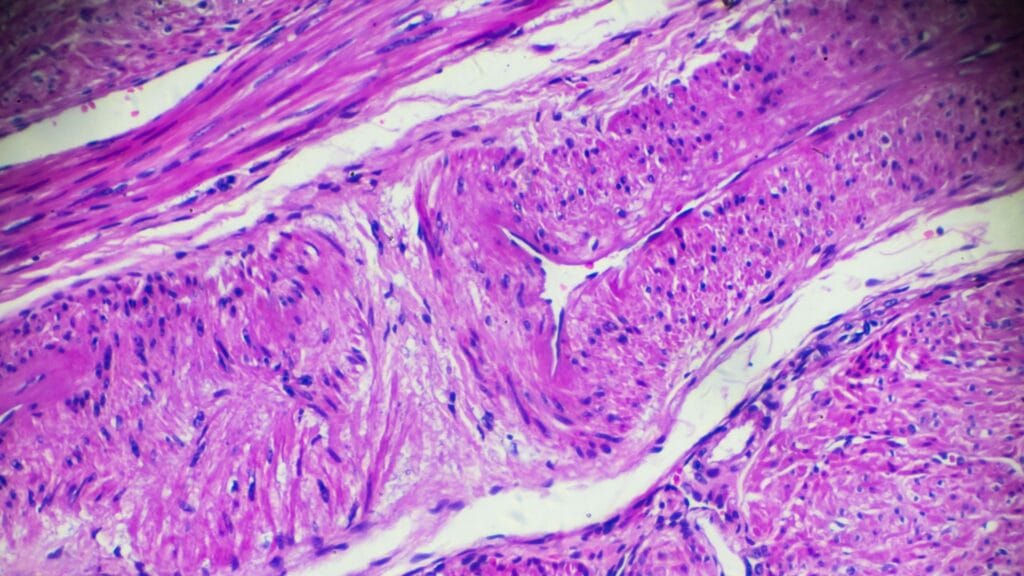

Czym jest zatem przerost endometrium? Jest to stan, w którym dochodzi do zmian morfologicznych w komórkach endometrium. Błona śluzowa staje się nadmiernie pogrubiona, a to niesie za sobą szereg poważnych konsekwencji. Niestety zmiany w endometrium mogą predysponować nawet do rozwoju raka endometrium, dlatego nie należy ich bagatelizować niezależnie od tego, czy planujesz ciążę, czy nie.

- Pobranie wycinków endometrium – najczęściej wykonuje się biopsję endometrium, która polega na pobraniu wycinków poprzez wprowadzenie specjalnej rurki (kaniuli Pipelle) do macicy poprzez szyjkę macicy. Biopsja wykonywana jest najczęściej u młodych kobiet, u których występują nieprawidłowe krwawienia z macicy, a czasem również przy PCOS i guzach jajników produkujących estrogeny. Inną, nieco dokładniejszą, ale bardziej inwazyjną metodą, jest pobranie wycinków z macicy pod kontrolą histeroskopii. Polega na wprowadzeniu histeroskopu przez pochwę i szyjkę macicy do jamy macicy i badaniu jej wnętrza za pomocą kamery. Jeśli lekarz zauważy nieprawidłowości, pobiera wycinki do badania histologicznego. Zabieg ten umożliwia precyzyjne pobranie materiału i jest wykonywany w znieczuleniu ogólnym.